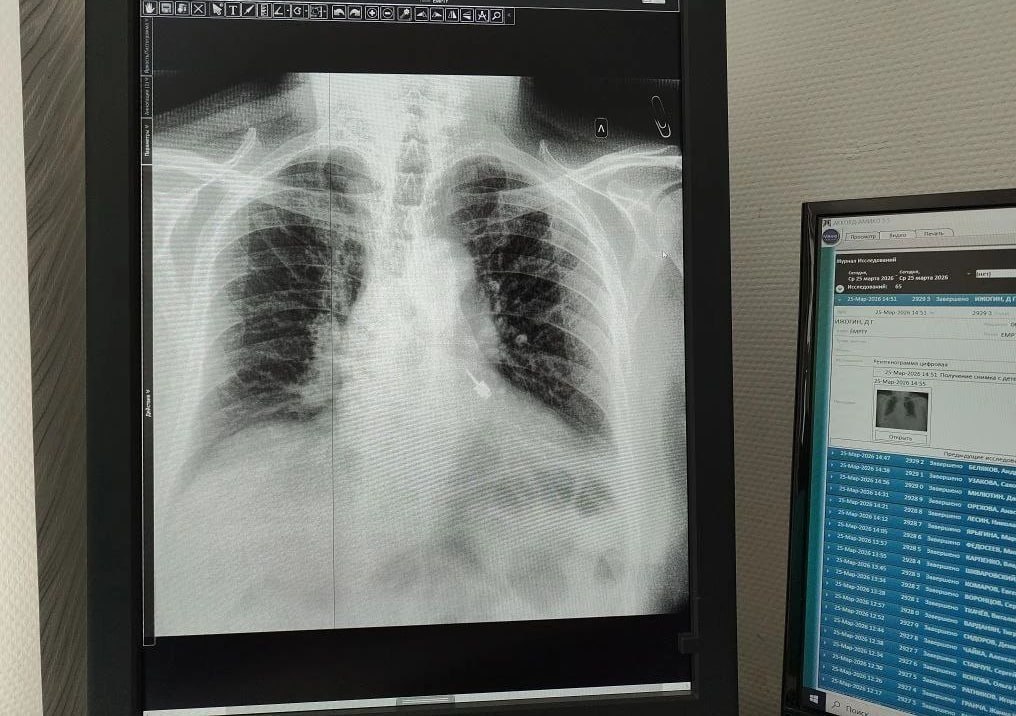

В Мытищинскую больницу экстренно доставили мужчину — во время лечения зубов в частной клинике стоматологический бур попал ему в дыхательные пути.Рентген показал, что острый инструмент застрял в левом бронхе. Любое промедление грозило кровотечением и...

Доставать его из бронха пришлось врачам.Операцию провели в Мытищинской областной больнице с помощью эндоскопа. С 82-летним мужчиной уже всё в порядке, его отпустили домой.Подписаться на RT:...

Во время приёма инструмент оказался в дыхательных путях мужчины. Он сразу почувствовал боль и отправился в больницу. Рентген показал, что бур находится в левом бронхе. Медики приняли решение экстренно прооперировать пациента, так как любое промедление...